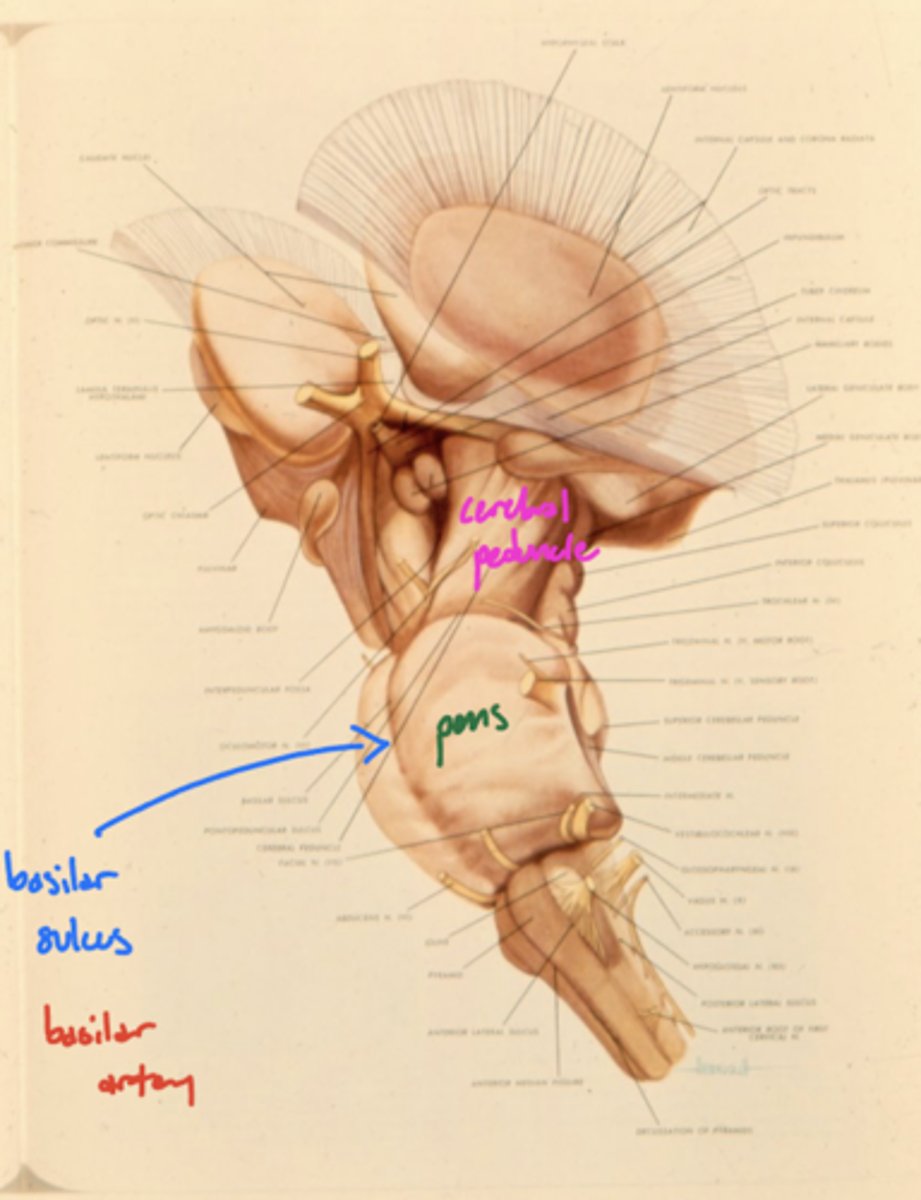

Where is the basilar sulcus?

ventral pons

What runs in the basilar sulcus?

basilar artery

What is the floor of the 4th ventricle?

tegmentum pons

image -- green

What cranial nerve nuclei are in the tegmentum pons?

1. CN V (5)

2. CN VI (6)

3. CN VII (7)

4. CN VIII (8)